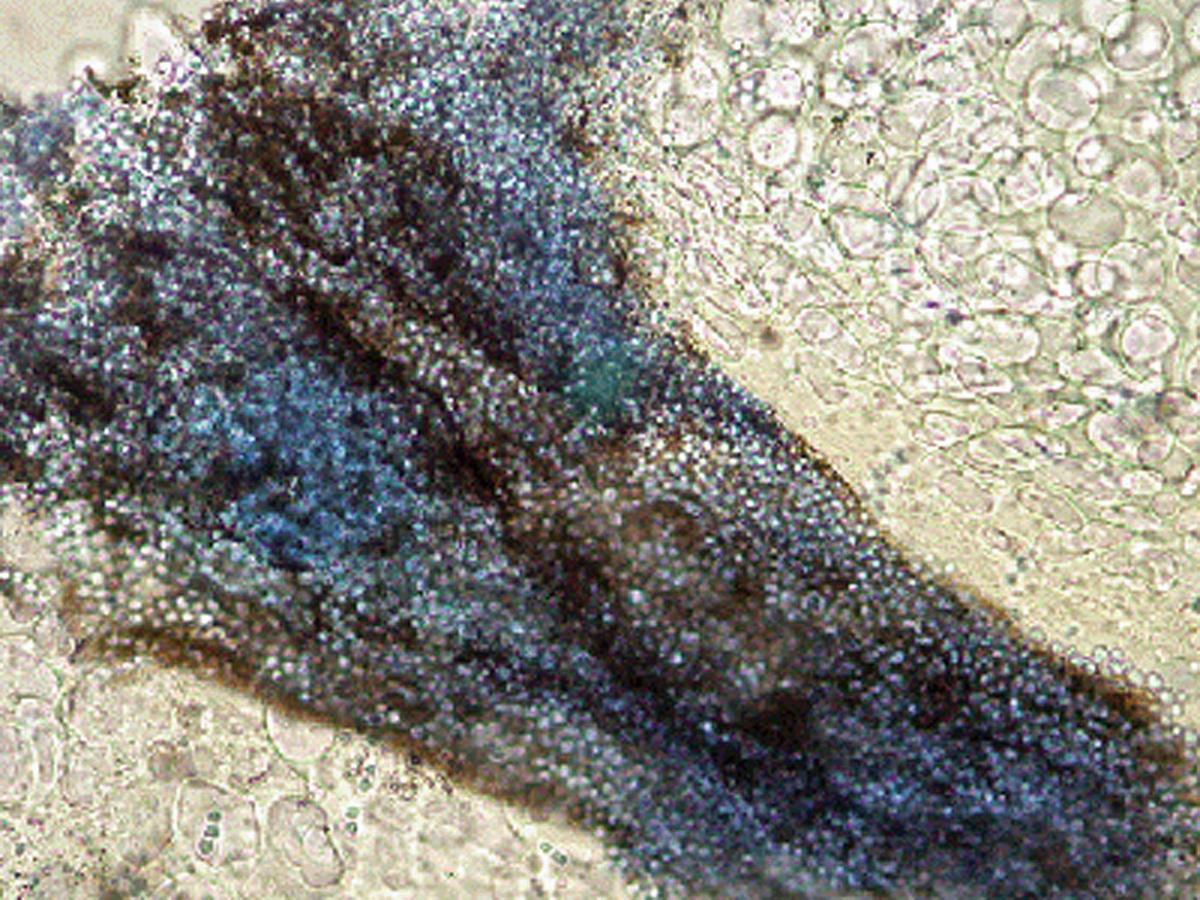

Unknown 06 direct microscopy of hair

Direct microscopy of hair